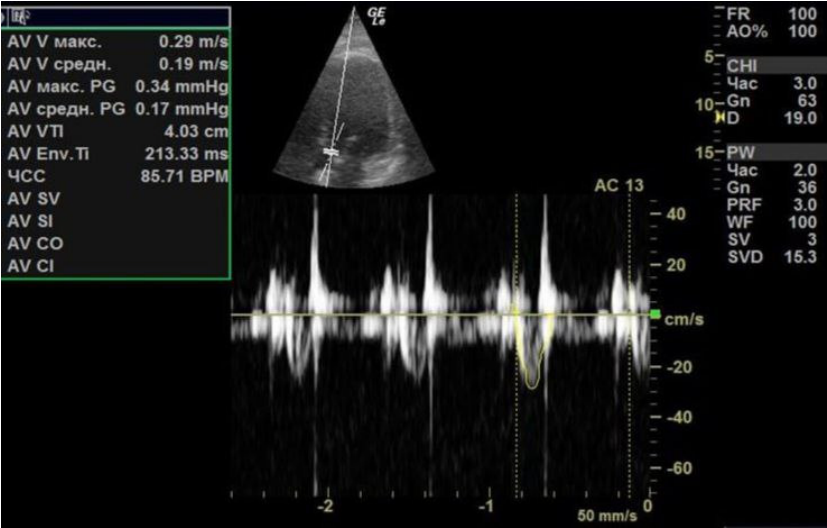

На фоне проводимой терапии кардиогенного шока, включавшей ЭКМО, катехоламины, отмечалась положительная динамика. В первые сутки ЭКМО ФВ ЛЖ cоставляла 30% с интегралом линейной скорости потока (velocity time integral, VTI) в выносящем тракте ЛЖ 4 см (рис. 2), отмечались признаки объемной перегрузки ЛЖ.

Рис. 2. В первые сутки ЭКМО.